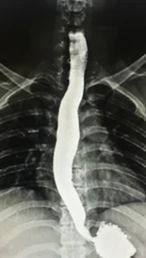

At Pulse Clinic, we are dedicated to providing comprehensive healthcare services that meet the diverse needs of our patients. With a team of highly skilled professionals and cutting-edge technology, we offer a wide range of medical services and diagnostic facilities to ensure your well-being. Here's an overview of the services we provide: